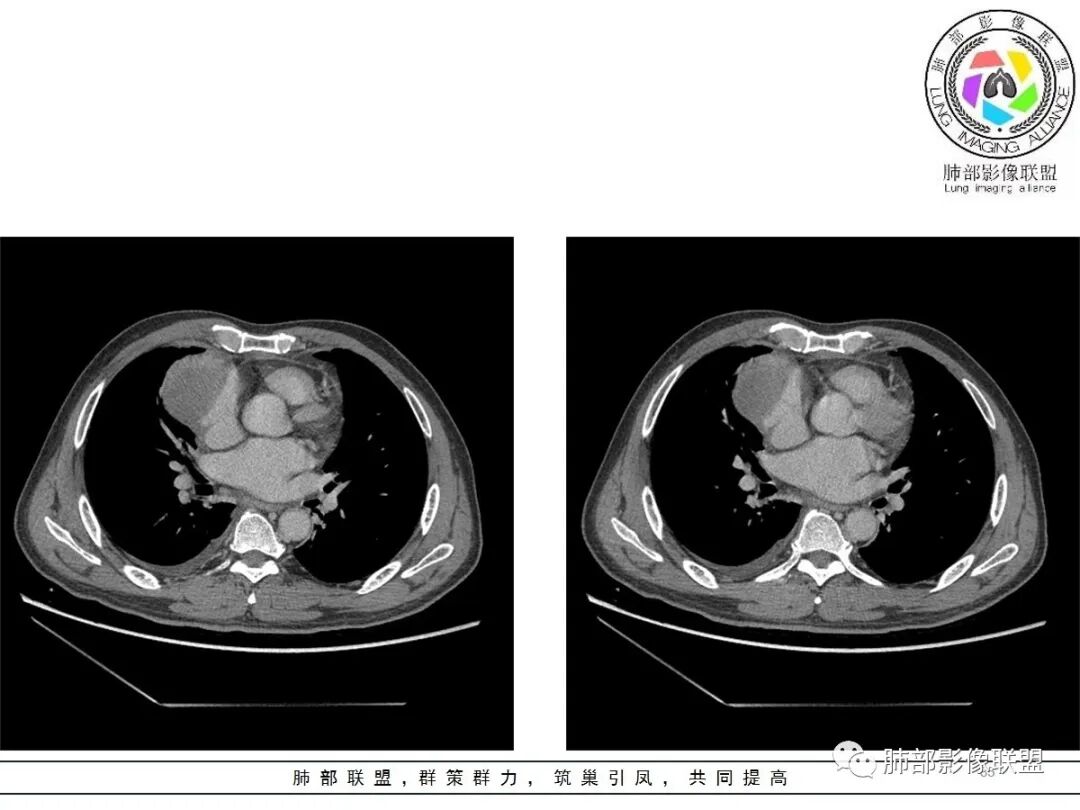

大雄:老年男性  急性起病 胸痛1天前纵隔占位伴右侧少量胸水,肿块整体膨隆,密度不均匀,可见坏死,纵隔脂肪间隙模糊不清常规考虑胸腺瘤/癌并梗死

一切∮随缘:定位肺外,病变位于右前纵隔,与肺部交接面清晰,有胸膜尾征,心包局部受压,部分包绕主动脉血管,平扫密度均匀,形态规则,膨胀性生长,增强扫描壁有强化,内容物无明显强化,考虑1:淋巴瘤2:胸腺瘤3:神经鞘瘤4:支气管囊肿

亚东:前纵隔囊实性肿物,形态尚规则 ,与心包分界不清,内可见小气泡,嚢内平扫密度低,强化不明显,囊壁强化,右胸腔积液,淋巴结肿大不明显,化验白细胞高,支持囊肿伴感染。

小强:前纵隔肿块,边缘模糊,其内有点状气体影,环形强化(肉芽肿?),心包胸膜受累,疾病谱:胸腺瘤(一般是侵袭性胸腺瘤累计心包,胸膜,强化不符合)淋巴瘤,生殖细胞瘤(年龄,AFP不高不负),考虑畸胎瘤,囊性畸胎瘤合并感染,边缘模糊,累计心包胸膜,3.19病变进展,胸腔积液,可能有破溃

采莲:老年男性,胸疼病史,右上前纵隔肿块,边缘光滑,平扫内部密度稍均匀,轻度强化,内有低密度区,与支气管关系不大,右侧少量积液。考虑来源纵隔,老年男性,胸腺瘤或胸腺癌,鉴别淋巴瘤。

修*:前纵隔偏右侧肿物,点状钙化,轻度强化,伴胸腔积液,考虑胸腺瘤B2型。

岁月:男性,68岁,右胸痛一天,无家族史,右上中叶纵膈旁占位;抽烟50年,3天1包。wbc高。与纵膈脂肪间隙不清,胸水,快进快出 分叶,有血管样强化,9.1-11.4-10.9。诊断:错构瘤,似乎都符合;但如果恶性放在前面,肉瘤、恶性。鉴别:错构瘤、侵袭性胸腺瘤;处理:经皮肺活检、手术。

王秀仙:右侧前纵膈肿块,密度不均,局部边缘可见点状钙化,其内可见点状低密度,与纵膈血管间脂肪间隙消失模糊,右侧胸腔积液,考虑纵膈畸胎瘤或皮样囊肿破裂。鉴别胸腺鳞癌。

必有路:老年人,右前纵隔占位,发病前纵隔脂肪干净,突发起病伴胸痛,白细胞增高病灶整体密度较为均匀,内有点状脂肪密度,位置个人觉得理胸腺区有点偏下,大部分囊性为主1、胸腺瘤伴突发梗死  突发起病,老年男,不支持点,位置偏下,囊变坏死太彻底,右侧胸廓内动脉没有增粗(实性肿瘤,往往会有间接供血增粗)倾向支持囊性病灶合并破溃感染2、囊性畸胎瘤伴破溃  影像上可以支持,脂肪含量比较少,发病年龄不太支持3、 皮样囊肿 可以有脂肪密度4、 支气管囊肿 理论上胸廓内都可以发生,肺内 后纵隔多见 张力大 圆5、心包囊肿  中纵隔更为多见综上,皮样囊肿>囊性畸胎瘤>胸腺瘤